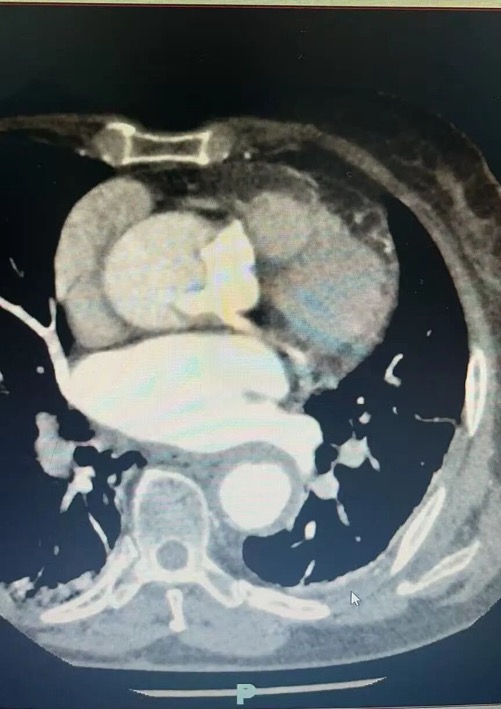

近日,84岁的李奶奶(化名)正在家中休息,突然感到一阵 "撕裂样"的胸背部剧痛,疼痛程度达到难以忍受的10级!家人立即将她送往邳州当地医院,经主动脉CTA检查确诊为 "主动脉夹层A型"——这个被称为"血管炸弹"的急症,死亡率高达每小时1%-2%!

更危急的是,进一步检查发现李奶奶还合并有冠心病(前降支重度狭窄),这意味着她的心脏随时可能因夹层破裂或心肌梗死而停跳。 "必须立即手术,但84岁高龄能否承受?" 带着这个疑问,家属决定转往徐州新健康心血管病医院进行治疗。